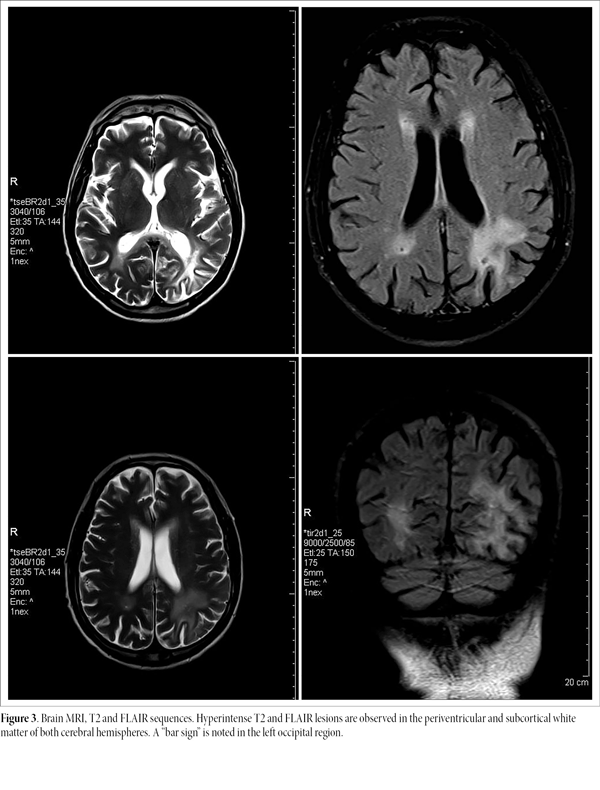

Laboratory results included CD4⁺ count = 161 cells/mm³ and HIV viral load = 35 copies/ml (previously 5940 copies/ml). MRI with contrast revealed hyperintense T2 and FLAIR lesions in periventricular and subcortical white matter bilaterally, with a “bar sign” in the left occipital region, without hemorrhagic collections or mass lesions (Fig. 3).

Figure 3. Brain MRI, T2 and FLAIR sequences. Hyperintense T2 and FLAIR lesions are observed in the periventricular and subcortical white matter of both cerebral hemispheres. A “bar sign” is noted in the left occipital region.